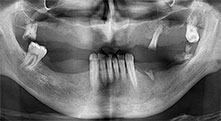

Pr Bratu : Nous utilisons couramment les instruments pour le prélèvement des blocs osseux et le clivage de la crête alvéolaire. Nous utilisons également les scies B6/B7 Piezomed pour l'ostéotomie des dents endommagées et l'extraction des implants défaillants. Bref, toutes les indications qui nécessitent des coupes profondes et propres.

Pr Bratu : Nous préférons prélever l'os sur la crête oblique externe de la mandibule postérieure, et non dans la région interforaminale. Après l'incision des tissus mous, nous utilisons les nouvelles scies pour définir la quantité d'os à prélever. De la même manière, nous les utilisons également pour la totalité de la préparation dans presque 80 % des cas. Nous avons également parfois recours à d'autres instruments piézoélectriques et, pour terminer, à un burin pour mobiliser le bloc. Nous trouvons cette technique chirurgicale très efficace.

Pr Bratu : Nous avons volontiers recours à la technique sandwich pour les augmentations mandibulaires latérales. La préparation d'un couvercle osseux est réalisée à l'aide de la scie piézoélectrique et le fragment crestal est fixé à l'aide de microvis. Nous plaçons un mélange de matériau de substitution osseuse autologue et xénogénique entre les deux. Cela fonctionne très bien. Il faut toujours s'assurer que les coupes verticales aient des dimensions suffisantes lors du clivage de la crête alvéolaire dans la mandibule. Sinon, l'os risque de se casser facilement.

Pr Bratu : J'estime que la chirurgie piézoélectrique a fait faire un grand bon en avant à la chirurgie orale. Grâce à cette technique, la préparation osseuse est plus sûre et plus facile. Par exemple, les extractions entraînent une perte osseuse minime. C'est très important d'un point de vue esthétique, surtout si la pose d'implants est prévue immédiatement.